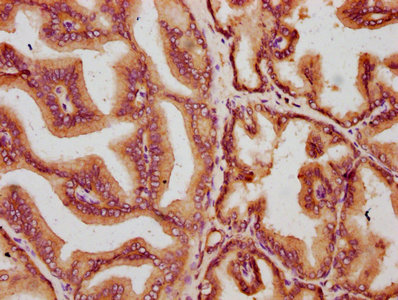

IHC image of CSB-PA890926LA01HU diluted at 1:400 and staining in paraffin-embedded human prostate tissue performed on a Leica BondTM system. After dewaxing and hydration, antigen retrieval was mediated by high pressure in a citrate buffer (pH 6.0). Section was blocked with 10% normal goat serum 30min at RT. Then primary antibody (1% BSA) was incubated at 4°C overnight. The primary is detected by a biotinylated secondary antibody and visualized using an HRP conjugated SP system.